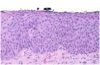

Describe this image:

Normal squamous epithelium

What is shown in this image?

Dysplastic squamous epithelium